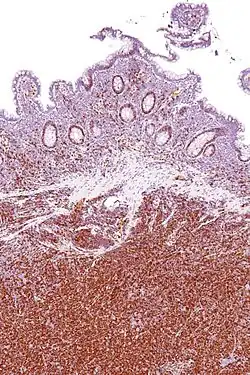

Immunohistochemical staining of cyclin D1 antibodies is used to diagnose mantle cell lymphoma.

Chromosomal translocation around the cyclin D1 gene locus is often seen in B mantle cell lymphoma. In mantle cell lymphoma, cyclin D1 is translocated to the IgH promoter[56] leading to cyclin D1 overexpression. Chromosomal translocation of the cyclin D1 gene locus is also observed in 15–20% of multiple myelomas.[57][58]